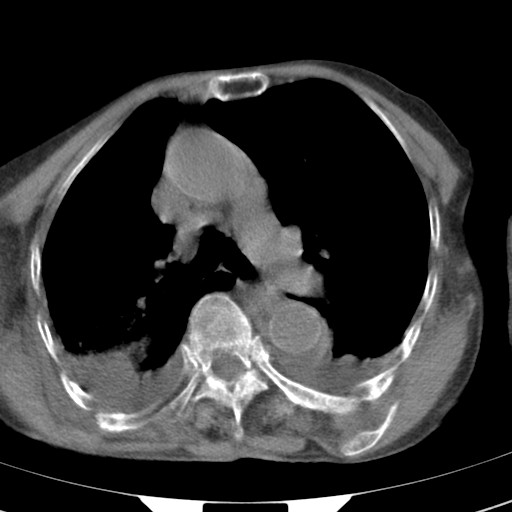

标题: CT21467:女,93岁,摔伤后检查。 [打印本页]

女,93岁,摔伤后检查。

右肺炎症,心功能不全伴双侧胸腔积液,右下肺膨胀不全,食管裂孔疝,冠脉钙化,心包少量积液,左侧肋骨骨折,请上传骨窗.

右侧锁骨\\肩胛骨骨折、右侧湿肺,心功能不全伴双侧胸腔积液,右下肺膨胀不全,左膈破裂或食管裂孔疝,冠脉钙化,心包少量积液,请上传骨窗.

右肺炎症,心功能不全伴双侧胸腔积液,右下肺膨胀不全,食管裂孔疝,冠脉钙化,心包少量积液,左侧肋骨骨折,右肩甲骨粉碎性骨折。93岁,高寿哇!

右肺炎症,心功能不全伴双侧胸腔积液,右下肺膨胀不全,食管裂孔疝,冠脉钙化,心包少量积液,左侧肋骨骨折,右肩甲骨粉碎性骨折。